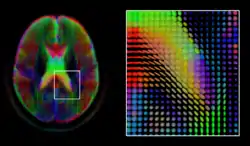

Medical image computing and imaging informatics

Imaging informatics and medical image computing develops computational and mathematical methods for solving problems pertaining to medical images and their use for biomedical research and clinical care. Those fields aims to extract clinically relevant information or knowledge from medical images and computational analysis of the images. The methods can be grouped into several broad categories: image segmentation, image registration, image-based physiological modeling, and others.